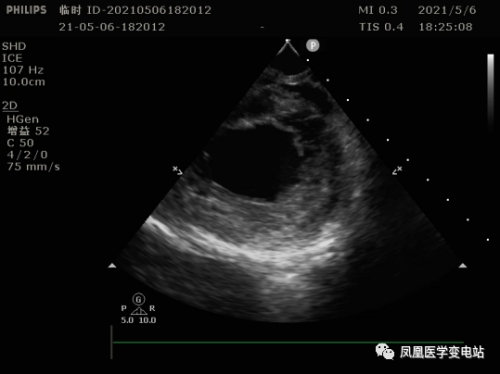

为防止术中出现卒中的可能,同时需术前评估左心耳及左心房的情况,必须搞清楚房颤患者心房是否出现血栓,食道超声检查显得十分必要。可该患者却无法耐受食道超声。刘燕锋向患者及家属建议,只能选择在术中使用超声导管,通过超声导管,一可以检查病人左心耳及左心房有无血栓;二可以指导房间隔的穿刺,由于右位心患者与正常人不同,使用超声导管协助手术可以降低手术难度,保证手术安全;三是术中可以实时监测心包有无积液。

镜面转位后,术中房间隔穿刺